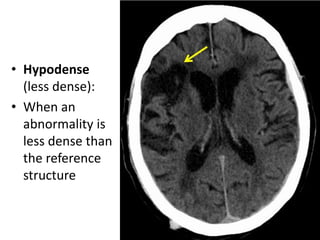

Read the information on the CT scan Do not get disoriented Hold the film in the proper orientation Follow the IV contrast filled Aorta as we descend caudally. CT scans of the mediastinum are reconstructed filmed and interpreted in an axial format. The mechanism is based on a quickly rotating narrow beam of x-rays directed towards a patient that produces signals that are processed by the machines software.